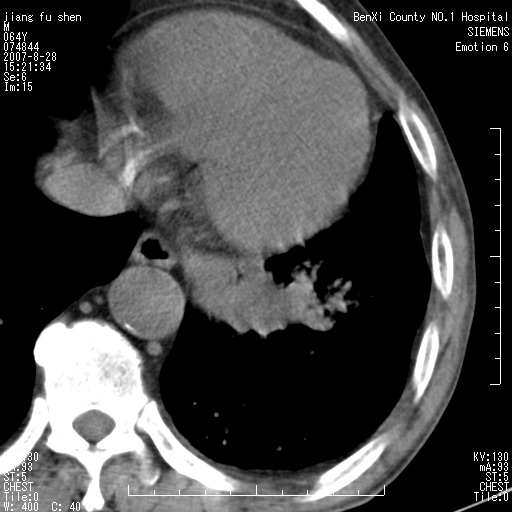

男、64、咳嗽、发烧一周、左肺呼吸音稍弱。既往肺结核,右手结核。

本次扫描患者未带原片,左肺下叶发现病灶。左肺上叶空洞,5组淋巴结肿大,1cm左右。

平扫20-33hu

增强31-33hu

1分半44-52

2分55-67

左肺下叶前内基底段支气管明显偏心性狭窄,周围分叶状肿块,伴有阻塞性肺炎,支持肺癌可能性大。

考虑左肺中央型肺癌并阻塞性肺炎

病灶边缘可见多量较长棘影及纤维条索状影,除外病灶边缘较光整,病灶有分叶表现,但多表现为较浅分叶,且向周围伸出之叶多呈尖角改变,且边缘较光整,病灶增强呈中度延时增强,且早期及中期仅轻度增强,结合患者病史,多考虑继发型肺结核,炎性增殖灶形成,不除外肺癌

左下叶支气管变窄,管腔光滑。软组织形状不规侧,分叶呈角形。结合病史考虑结核可能性大。肺癌不除。